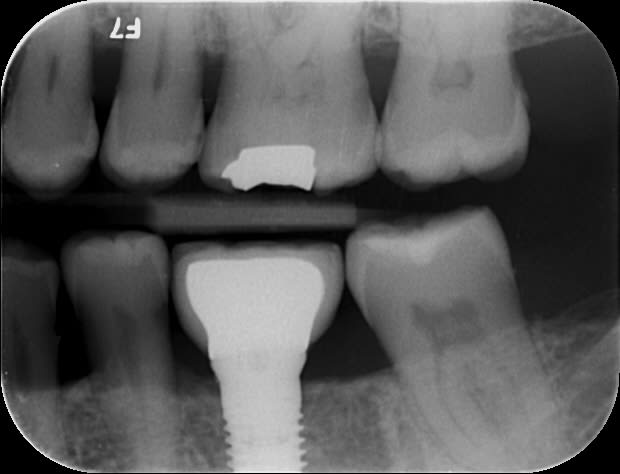

Voici 3 Rx d'un petit cas tout simple : implant Replace Nobel avec pilier titane ID.

Bite-wing fait au contrôle à 1 an. Pour ceux qui douteraient de la compatibilité parfaite :-)